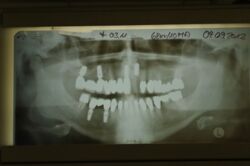

Kieler Patient erhält implantatgetragene Frontzahnbrücke

Dieser Patient fällt ein bißchen aus dem üblichen Rahmen, weil die vielfachen Versorgungen hier nicht zeigtlich im Rahmen einer CMD Behandlung erbracht wurden, sondern über viele Jahre hinweg nach und nach.

Der Patient wurde von dem Praxisvorgänger übernommen und befindet sich daher seit weit über 20 Jahren hier in Behandlung.